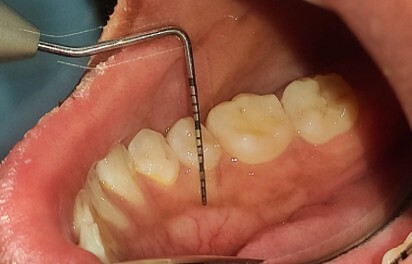

The MGJ was delineated by the visual method and the roll method following clinical examination in dental chairs appropriately equipped. Visual assessment relies on identifying the color difference between the gingiva and alveolar mucosa. The mucosa beyond the MGJ typically appears darker red compared to the AG, helping to demarcate the MGJ. The rolling probe method entails pushing the neighboring alveolar mucosa coronally with the blunt end of a probe. It is a functional assessment method that aids in determining the boundary between gingiva and movable mucosa.10 The probing sulcus depth was subtracted from the measured KG width at the mid-lingual aspect of each tooth to determine the width of AG, and all fractional measurements were rounded off to the nearest whole number of millimeters (Figure 1 through Figure 3).

Fig 1 through Fig 3. Measurements of lingual attached gingiva: Fig 1 = identifying the MGJ.

Figure 1

Fig 2 = sulcus depth measurement.

Figure 2

Fig 3 = determining width of keratinized gingiva.

Figure 3